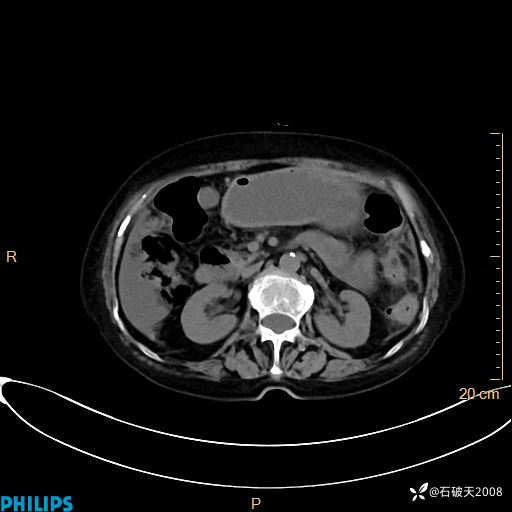

静脉期